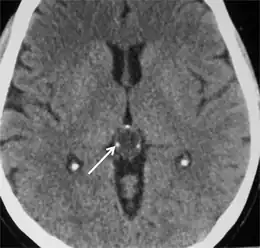

Pineocytoma in a 35-year-old person